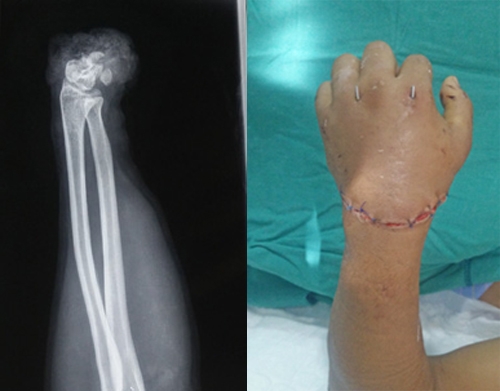

Anh Minh Hoàng bị bắn trọng thương (Ảnh: Zing news) |

Một lúc sau, anh Hoàng bị 2 thanh niên xông đến dùng mã tấu chém liên tiếp vào người, tay. Hoảng sợ, nạn nhân bỏ chạy, khi về đến nhà thì gục xuống. Anh này được người thân đưa đi cấp cứu.

Sau khi lời qua tiếng lại, một tên trong nhóm thanh niên rút khẩu súng bắn 3 phát vào người anh Minh Hoàng. Trong đó một phát trúng ngực, một phát trúng cằm, phát thứ 3 trượt qua đầu.

Theo các bác sĩ Bệnh viện tỉnh Khánh Hòa, anh Nhật Hoàng sau khi được khâu vết thương đã tỉnh táo. Còn nạn nhân Minh Hoàng đang chờ phẫu thuật gắp mảnh đạn, sức khỏe đang phục hồi tốt.